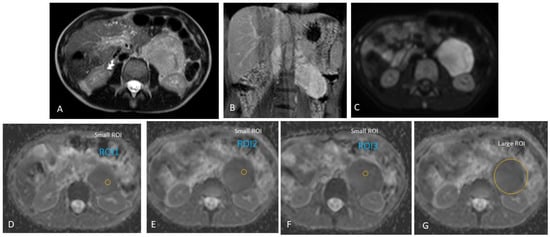

2.3.2. MRI Interpretation